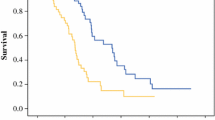

The computed ROC yielded an AUROC of 0.788 (95% confidence interval [CI] 0.686–0.873). The optimal threshold of differentiation was 2.925. At this threshold, 37 of 70 (53%) examinations had FLAIR SI in the tumor resection cavity greater than 2.925. Of these, 26 were from the ePD group and 11 were from the PsP group. The remaining 33 (47%) examinations were below the threshold. Of these, 7 were from the ePD group and 26 from the PsP group. (See Figs. 3 and 4). The corresponding sensitivity and specificity at the optimal cutoff were 0.818 and 0.694, respectively. See Fig. 5.

Subgroup analysis of biopsy-confirmed cases of PsP yielded an AUROC of 0.856 (95% CI 0.769–0.932), a sensitivity of 0.667, and a specificity of 0.957 at an optimal threshold of 4.147. When inclusion was restricted to clinically confirmed cases of PsP, subgroup analysis resulted in an AUROC of 0.667 (95% CI 0.490–0.819), a sensitivity of 0.788, and a specificity of 0.615 at an optimal threshold of 2.805. Results are summarized in Table 1.